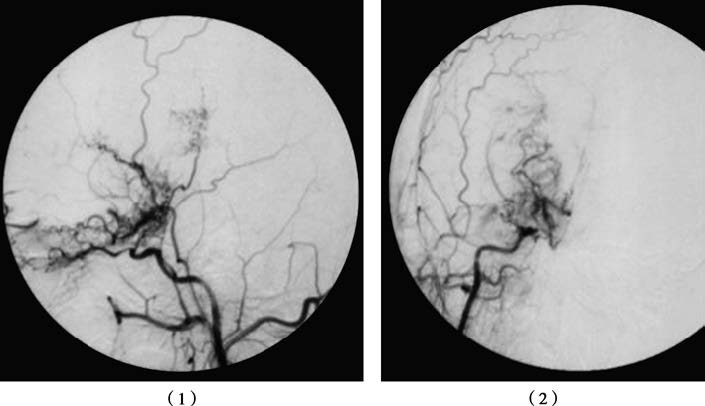

Cerebral digital subtraction angiography (DSA) typically shows stenosis or occlusion of the supraclinoid segment of the internal carotid artery. Thin abnormal vascular networks in the basal ganglia exhibit a "smoke-like" appearance. Extensive vascular collateralization is often seen, including networks between the posterior cerebral artery and the pericallosal artery, as well as connections between the external carotid artery and the temporal artery. Angiography aids not only in diagnosing MMD but also in identifying suitable donor vessels for revascularization surgery and detecting associated aneurysms.

Figure 1 Moyamoya disease

DSA imaging of the right common carotid artery demonstrates occlusion of the right middle cerebral artery with moyamoya-like vascular formation at the terminal segment of the internal carotid artery: (1) lateral view of the right common carotid artery; (2) frontal view of the right common carotid artery.